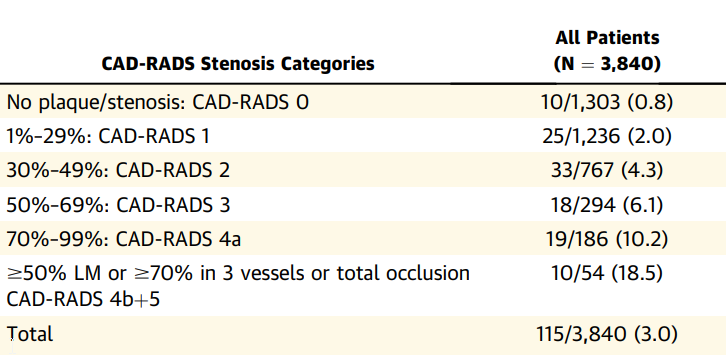

Risque à 5 ans d’événement CV

https://www.jacc.org/doi/pdf/10.1016/j.jcmg.2019.09.012